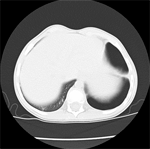

We asked for a Chest CT scan